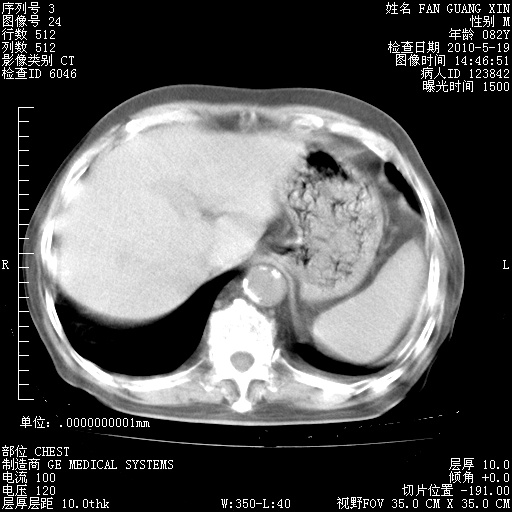

治疗3周后的肺部CT纵隔窗

再治疗10天后的肺部CT

再治疗10天后的肺部CT 纵膈窗

阅读此次胸部CT,肺间质渗出性改变较入院时有吸收。目前从体温、白细胞、中性分叶明显增高,肯定存在细菌感染(发生医院感染哦,若无消化道及泌尿系统等感染的依据,肺部感染可能大)。若你院头孢哌酮舒巴坦钠耐药率较高,同意你的方案,若48小时体温仍高,可考虑使用碳青霉稀类抗菌药物,同时可予超声雾化、注意滴数时加大液体量。白蛋白33.30g/L较低哦,需加强营养等支持治疗。